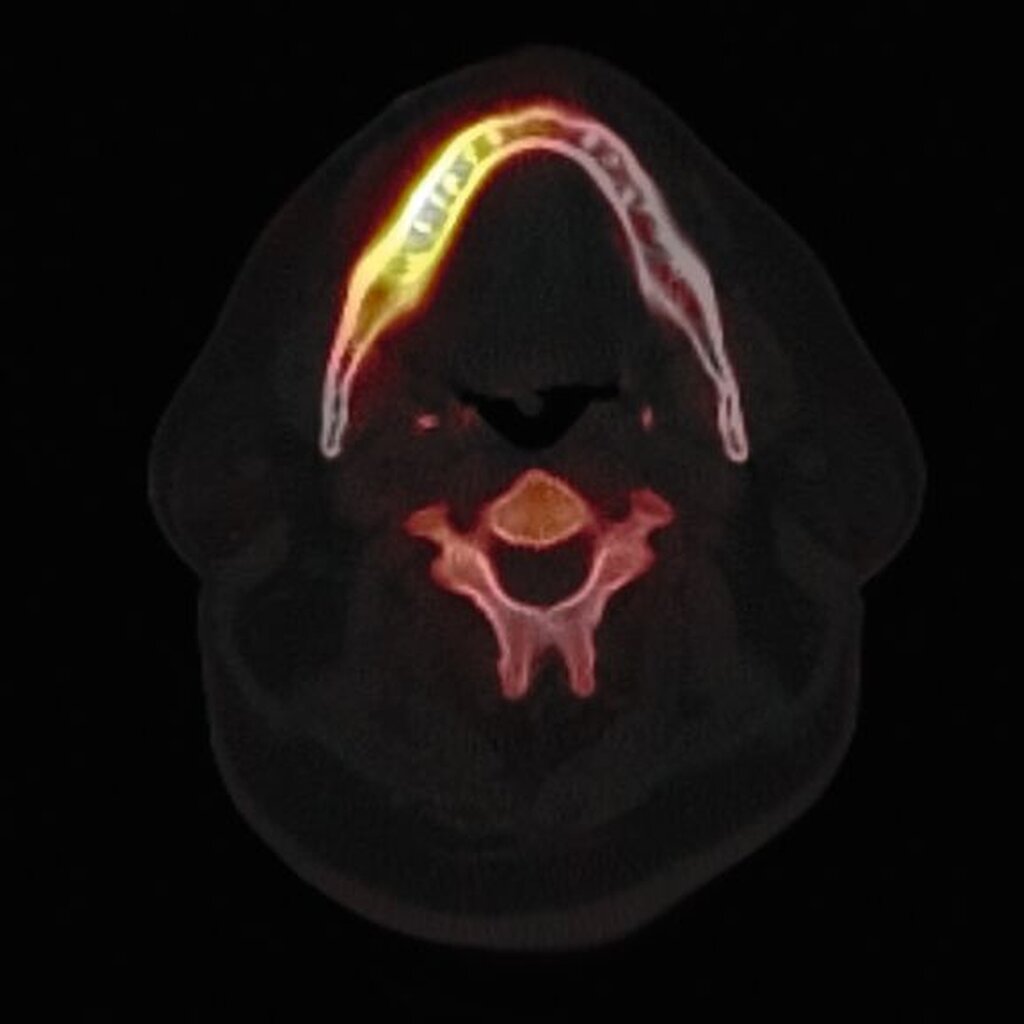

Zum Zeitpunkt der Erstvorstellung in der kieferchirurgischen Ambulanz zeigten sich keine klassischen Herpes-Zoster-Effloreszenzen im Gesicht. Eine antiresorptive Therapie oder Bestrahlung lag nicht vor, sodass eine Herpes-Zoster-assoziierte Osteonekrose im Sinne einer Ausschlussdiagnose festgestellt wurde. Anamnestisch bestand ein gut eingestellter Diabetes mellitus Typ 2 als potenziell immunkompromittierende Grunderkrankung. Die Knochenszintigrafie zeigte eine deutliche Stoffwechselsteigerung im betroffenen Bereich, vereinbar mit einer infizierten Osteonekrose.

Therapeutisch erfolgte eine gezielte Sequestrotomie und nur zwei Zahnentfernungen. Auf eine plastische Deckung wurde bewusst verzichtet. Stattdessen wurde Platelet-Rich Fibrin (PRF) auf die Wundfläche appliziert und mit einer Verbandplatte geschützt. Unter vorübergehender enteraler Ernährung über eine Magensonde zeigte sich eine nahezu vollständige Schleimhautregeneration innerhalb weniger Wochen. Eine kleine Restläsion in Regio 44 lingual heilte unter lokaler Therapie mit Chlorhexidin und einer Occlusivpaste vollständig ab. Eine Kontrollszintigrafie nach sechs Monaten bestätigte die weitgehende Ausheilung.

Die Knochenszintigrafie zeigte in diesem Fall eine deutliche lokale Mehranreicherung, wie man sie in vergleichbarer Intensität auch bei Medikamenten-assoziierten oder Strahlenbedingten Osteonekrosen beobachten kann. Während bei diesen Entitäten aufgrund der chronischen Ischämie meist ausgedehnte, teils kontinuitätunterbrechende Resektionen erforderlich sind, unterscheidet sich die Pathophysiologie der Herpes-Zoster-assoziierten Osteonekrose grundlegend. Da hier eine vorübergehende, Virus-induzierte Vaskulitis vorliegt, sollte die szintigrafische Aktivität nicht überinterpretiert, sondern ein zurückhaltendes, reduziert-invasives chirurgisches Vorgehen gewählt werden. Der beschriebene Heilungsverlauf bestätigt die Effektivität des gewählten konservativen Vorgehens.